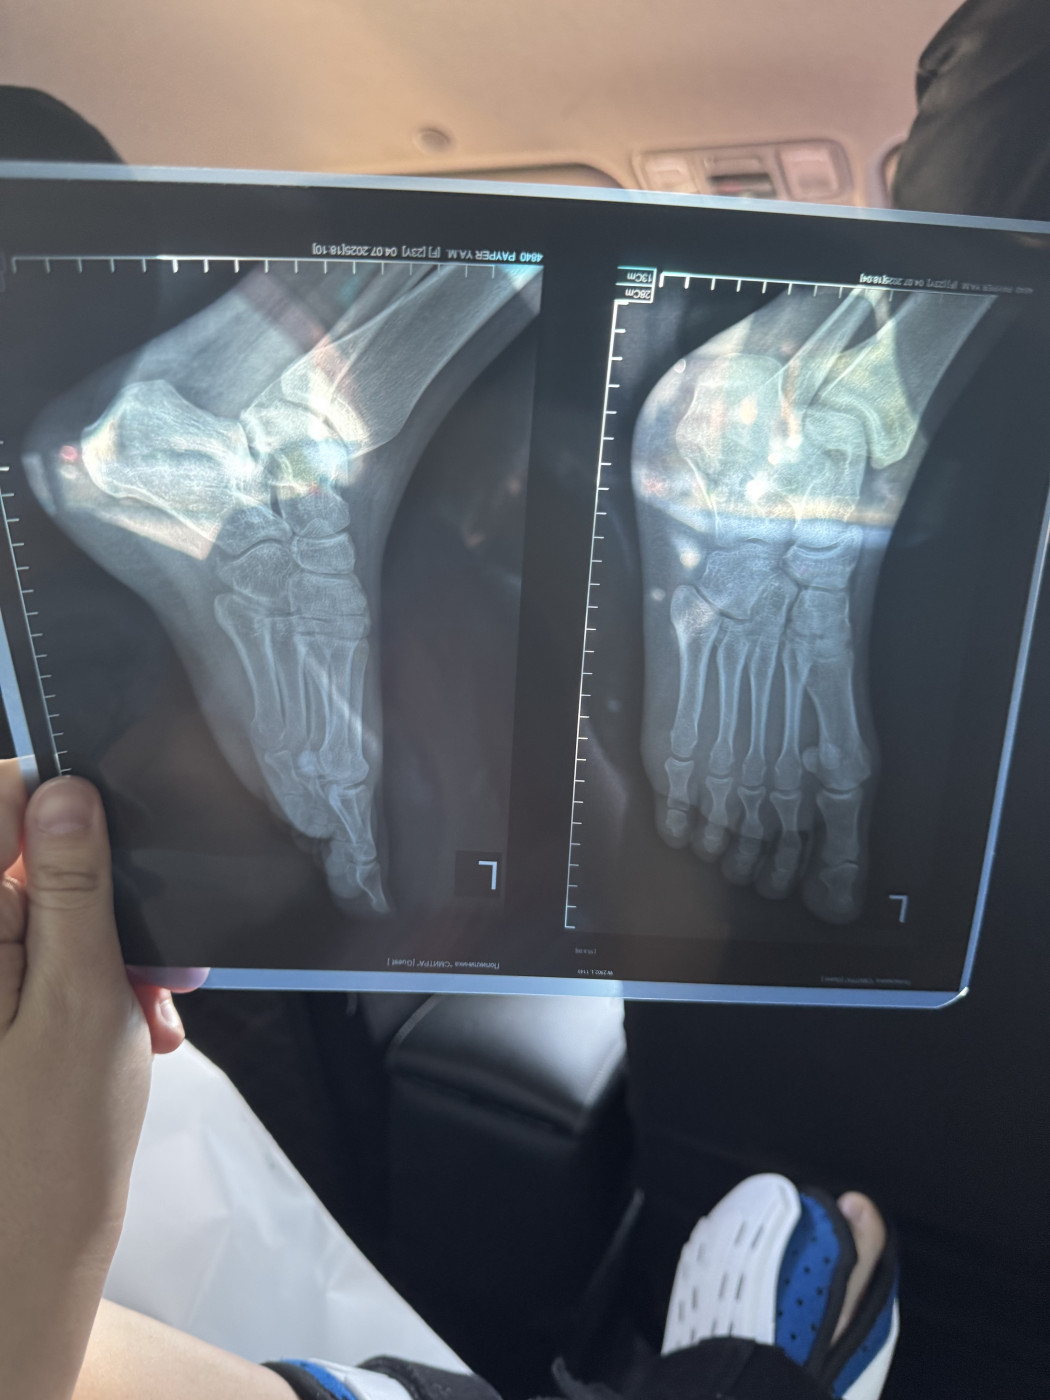

Жмет пластиковый ортезДобрый день! 3 ноября я сломала пятую плюсневую кость на левой ноге, перелом без смещения. Мне наложили гипс. 15 ноября после повторного рентгена (снимок от 15 ноября на фото) мне наложили пластиковый ортез ordect и сказали, что я могу ходить с опорой на пятку. Но этот ортез мне жмет, мизинец очень плотно прижат к другим пальцам. |